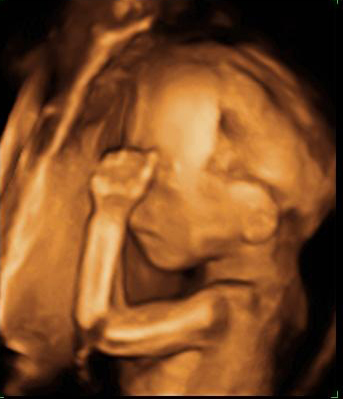

Ecografía Embarazo 4D Semana 20 - MALFORMACIONES FETALES